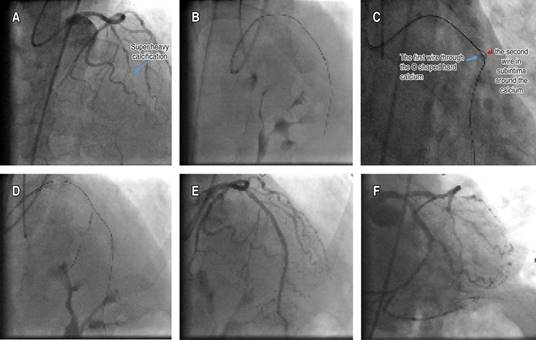

Figure 1: A) The blue arrow shows super heavy calcification. B) The wire could be advanced, but the microcatheter failed to pass the chronic total occlusion body. C) The blue arrow shows the second wire in the subintima around the calcium. D) Following balloon inflation in the subintimal area, the microcatheter then could be advanced with the support of an anchor balloon. E-F) Final appearances in cranial and caudal views.

Since the balloon uncrossable lesion was covered with a high calcium burden, cracking the calcification with a balloon advanced over a subintimal hydrophilic wire was another option. A fielder XT-A guidewire was advanced around the CTO lesion in the subintimal area (Figure 1C). A 2*12 mm balloon was inflated at 8 atm over the wire in the subintimal area to crack the calcification from outside. After extraluminal plaque modification, the subintimal wire and the balloon were withdrawn. A microcatheter was then advanced with the support of an anchor balloon over the original true lumen wire (Figure 1D). Then the procedure was successfully completed with balloon predilatation and stent implantation (Figure 1E-F).

A 66-year-old male with typical angina and a history of failed CTO percutan was referred to our CTO tertiary center for retry. Echocardiography revealed an ejection fraction of 45%. MRI study demonstrated viability in the LAD region. Coronary angiography revealed a long LAD CTO over 20 mm with heavy calcification (Figure 1A). The J-CTO score was four since the first attempt in another center had failed due to the inability of the wire passage.1 The cap of the CTO was semi-ambiguous. The wire was able to be advanced through the highly calcified lesion with the support of a microcatheter, but the microcatheter and even low-profile balloons could not be advanced despite good backup with 7 fr femoral access and an EBU catheter in place (Figure 1B). First of all, the microcatheter was exchanged with a more supportive one, and the calcified lesion was tried to be drilled. The second step was using a guide extension catheter in order to increase support. Upon failure, an anchor balloon was inflated in the septal branch. A blimp scoring balloon was used in combination with an anchor balloon and deep-seated guide extension.2 Leopard crawl technique and grenadoplasty were also tried, but both failed.3 The other options were the STAR technique, which will probably lead to the loss of many side branches, and the retrograde approach, with a low chance of success due to unfavorable collaterals. If we wanted to use a rotaablator, we first had to pass a rotawire through the microcatheter, and since the microcatheter could not be advanced, there was a risk of losing the original wire, which was in the true lumen due to the long distance of the CTO. Moreover, the patient refused.